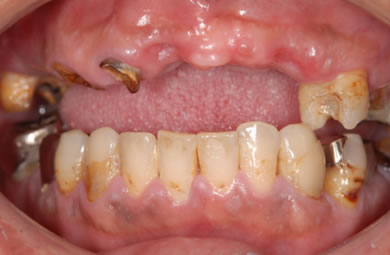

| 性別/年齢 | 男性 / 44歳 | ||||||||||||||||||||||||||||||||

| 主訴 | 前歯がぐらついている。 | ||||||||||||||||||||||||||||||||

| 治療方針 | 骨再生療法にて上顎の骨を増やしインプラント治療にて審美的・機能的回復を行う。 | ||||||||||||||||||||||||||||||||

| 治療内容 | インプラント7本(ソケットリフト)、ハイブリッドセラミック12本 | ||||||||||||||||||||||||||||||||

| 総治療費 | 3,207,924円 | ||||||||||||||||||||||||||||||||

| 治療期間 | 1年6ヶ月 |